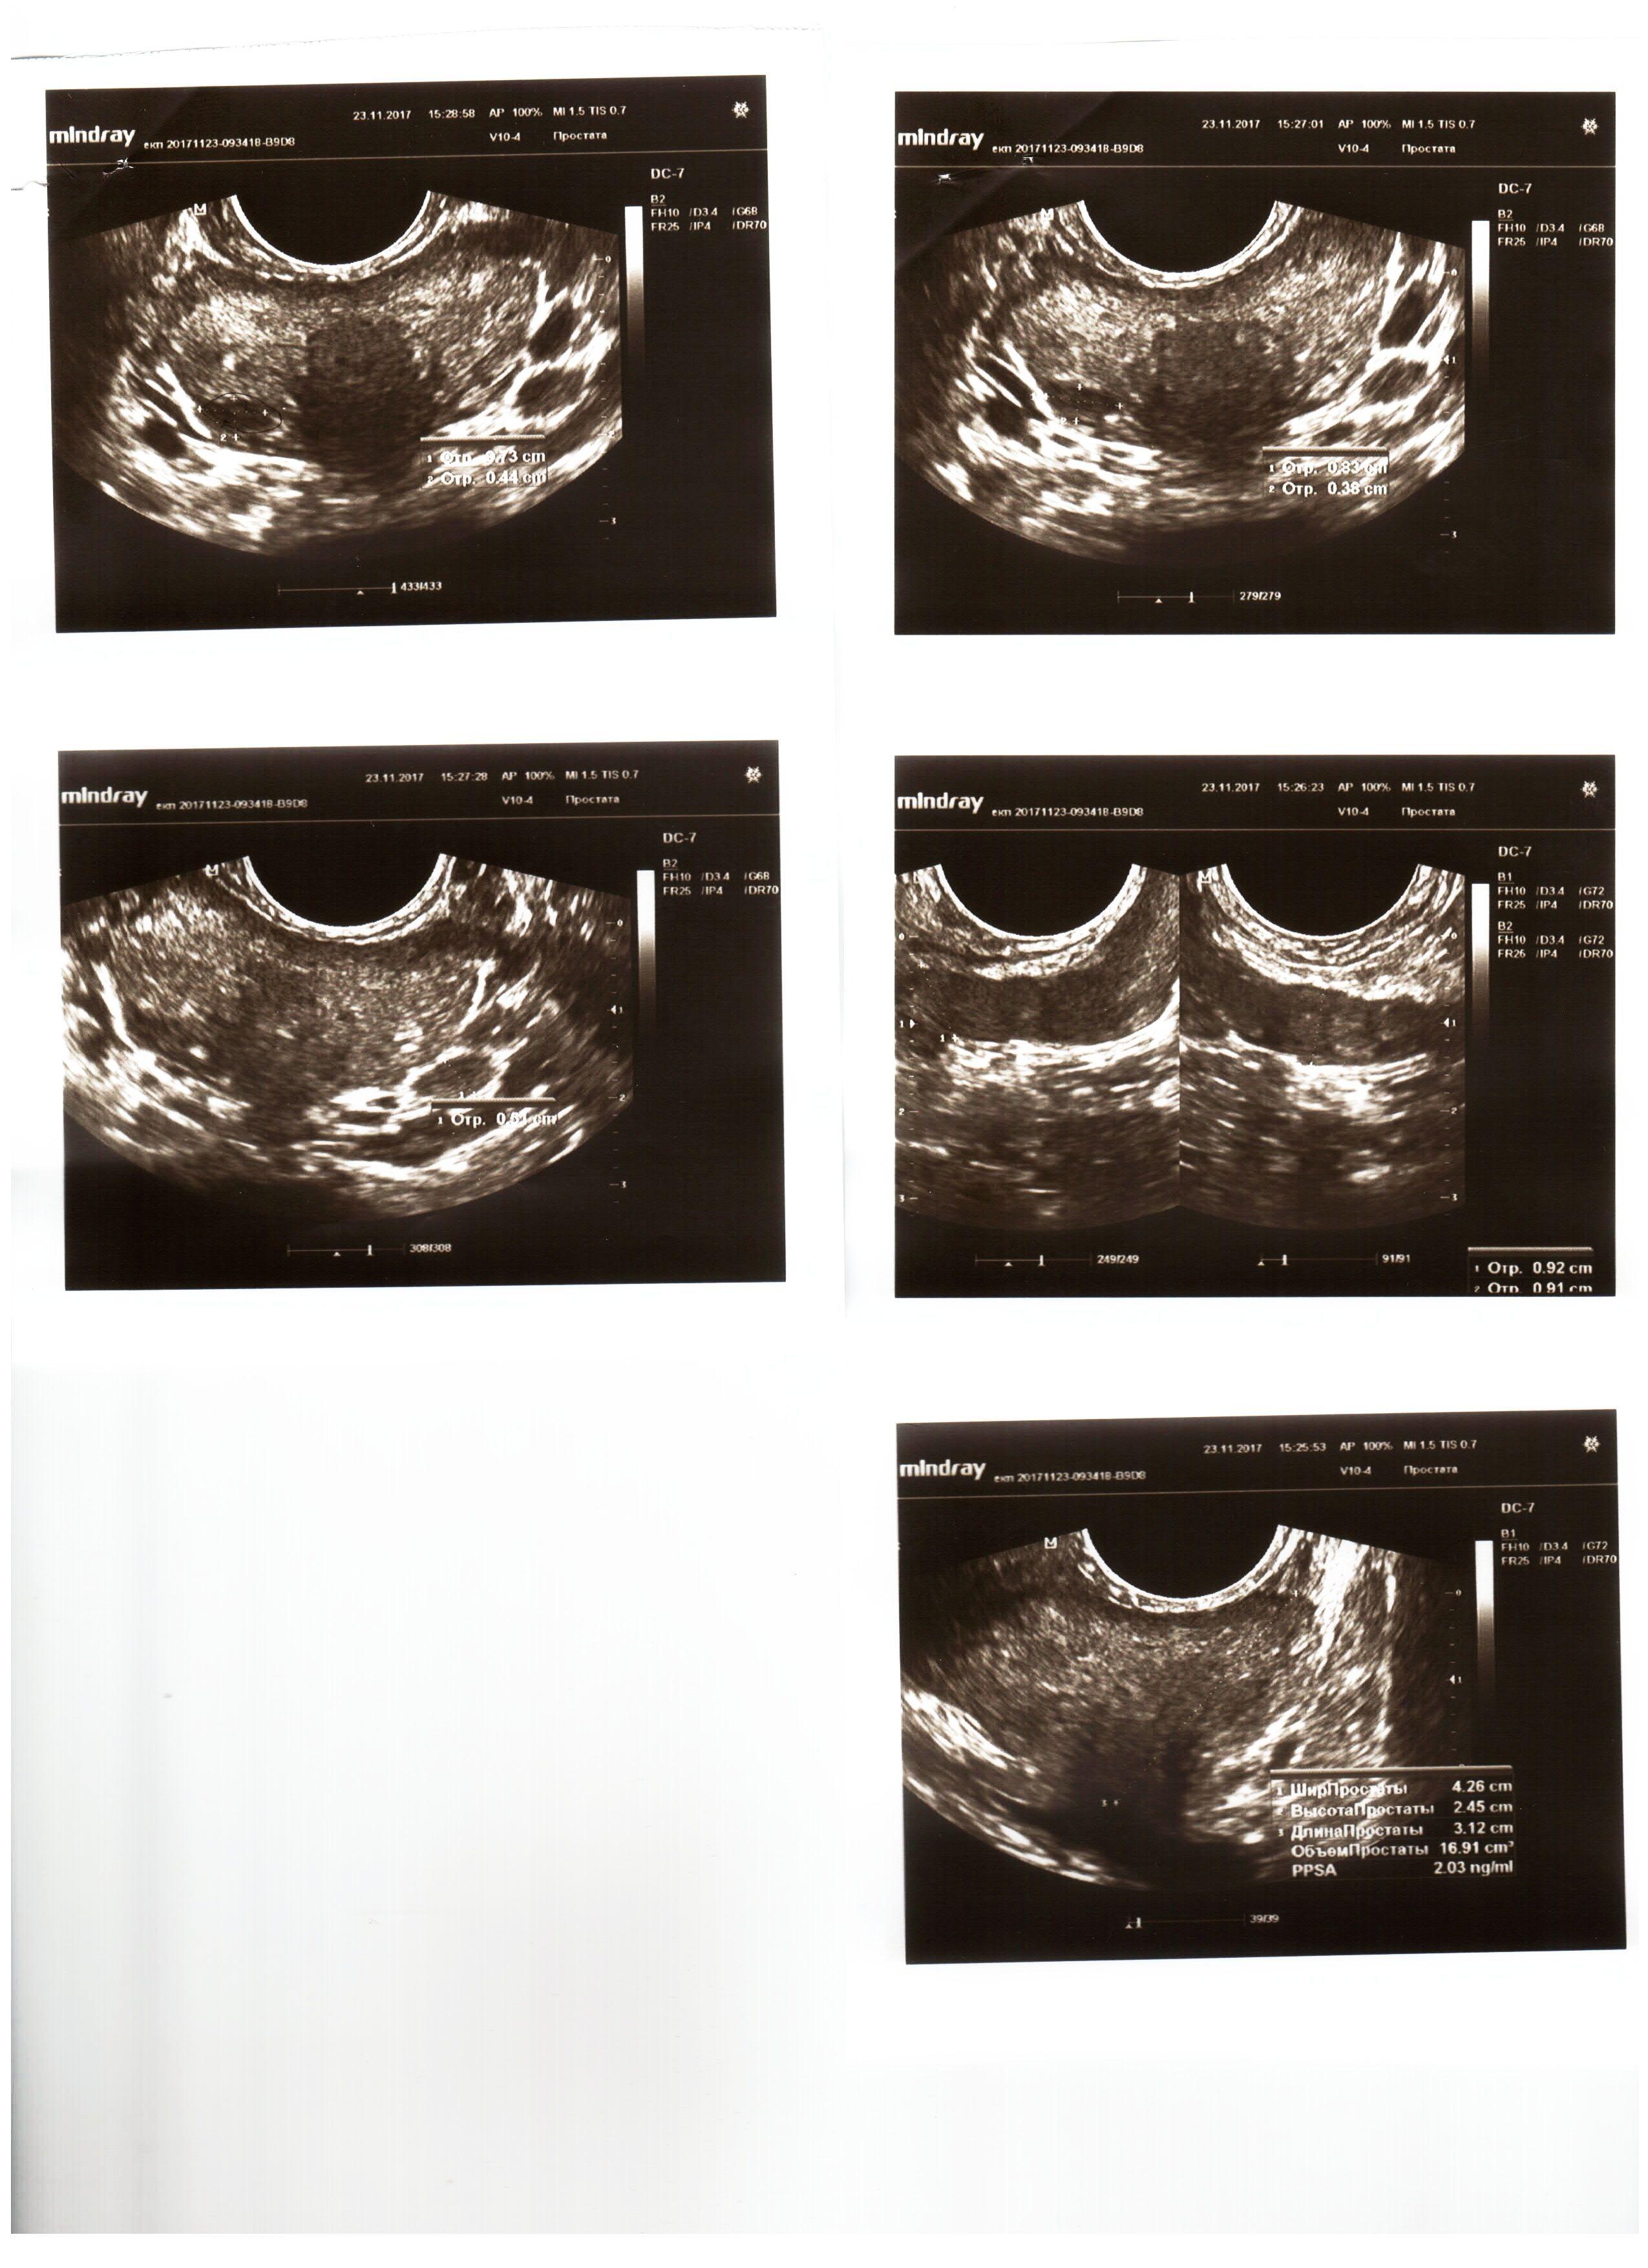

Болею с 21 августа 2017 г. Раньше болел 18 лет назад в течение 2-х лет, вылечился, вообще ничего не беспокоило. Никаких проявлений. Последние три года нерегулярная половая жизнь плюс эксцесс (очень интенсивный секс) в течение месяца (июль- август 2017). Госпитализировали на скорой с температурой 40, никаких болей при этом вообще не было, даже забыл и думать про простату. С тех пор прошел 2 курса вибро-магнито-лазерной терапии, два курса пальцевого ректального массажа, принимал массу различных антибиотиков, в данный момент пью Вобэнзим, ставлю свечи с Лонгидазой, в результате небольшое улучшение есть, беспокоят: отсутствие дневных эрекций + ежедневные ночные (3-5 утра), слабая струя мочи. Вопрос: на ТРУЗИ (в приложении) ипоэхогенный негомогенный участок 8,3 х 3,8 мм. Что это может быть и как уточнить? Врач ТРУЗИ сказала, что возможно, это рак. Или абсцесс. Что делать? Очень переживаю.